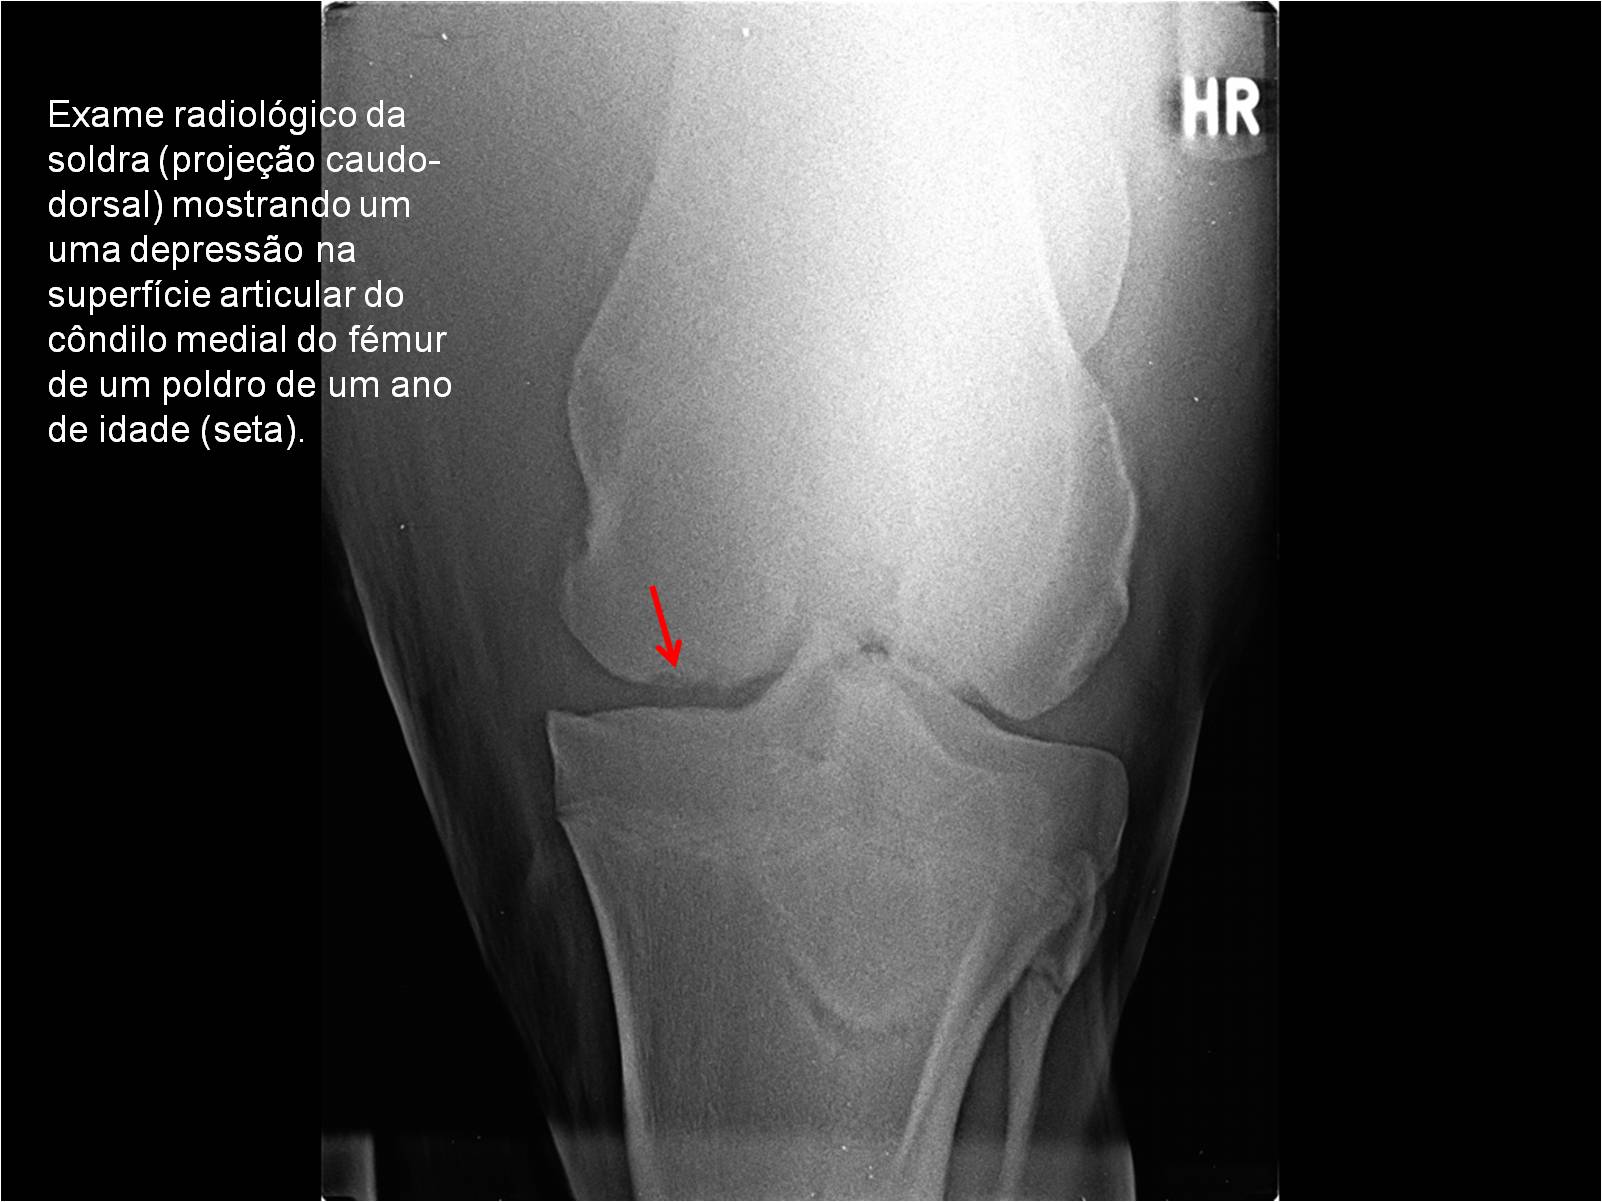

Publisher: Universidade de Évora

Abstract: O relatório de estágio encontra-se estruturado em três partes distintas. A primeira parte faz a caracterização das infraestruturas e funcionamento do Hospital Veterinário de Equinos de Lüsche, Oldenburg, Alemanha, assim como a análise casuística dos casos clínicos acompanhados durante os 6 meses de estágio. A segunda parte consiste de uma revisão bibliográfica sobre quistos do osso subcondral em equinos. Por fim, a terceira parte consta da apresentação e discussão de um caso clínico, nomeadamente o diagnóstico e acompanhamento imagiológico, por ressonância magnética, de um quisto subcondral na terceira falange num cavalo adulto; ### Abstract Equine Practice- Subcondral bone cyst of the third phalanx This internship report is divided in three parts. The first part characterizes the infrastructure and function of the Equine Hospital Lüsche, Oldenburg, Germany, as well as the casuistic of the clinical cases accompanied during the 6 month internship. The second part consists in a bibliographic review of cystic lesions of the subchondral bone in equines. The third part consists in a case report, the diagnostic and imagiological accompaniment, by use of magnetic resonance imaging, of a subchondral bone cyst in the distal phalanx of an adult equine.